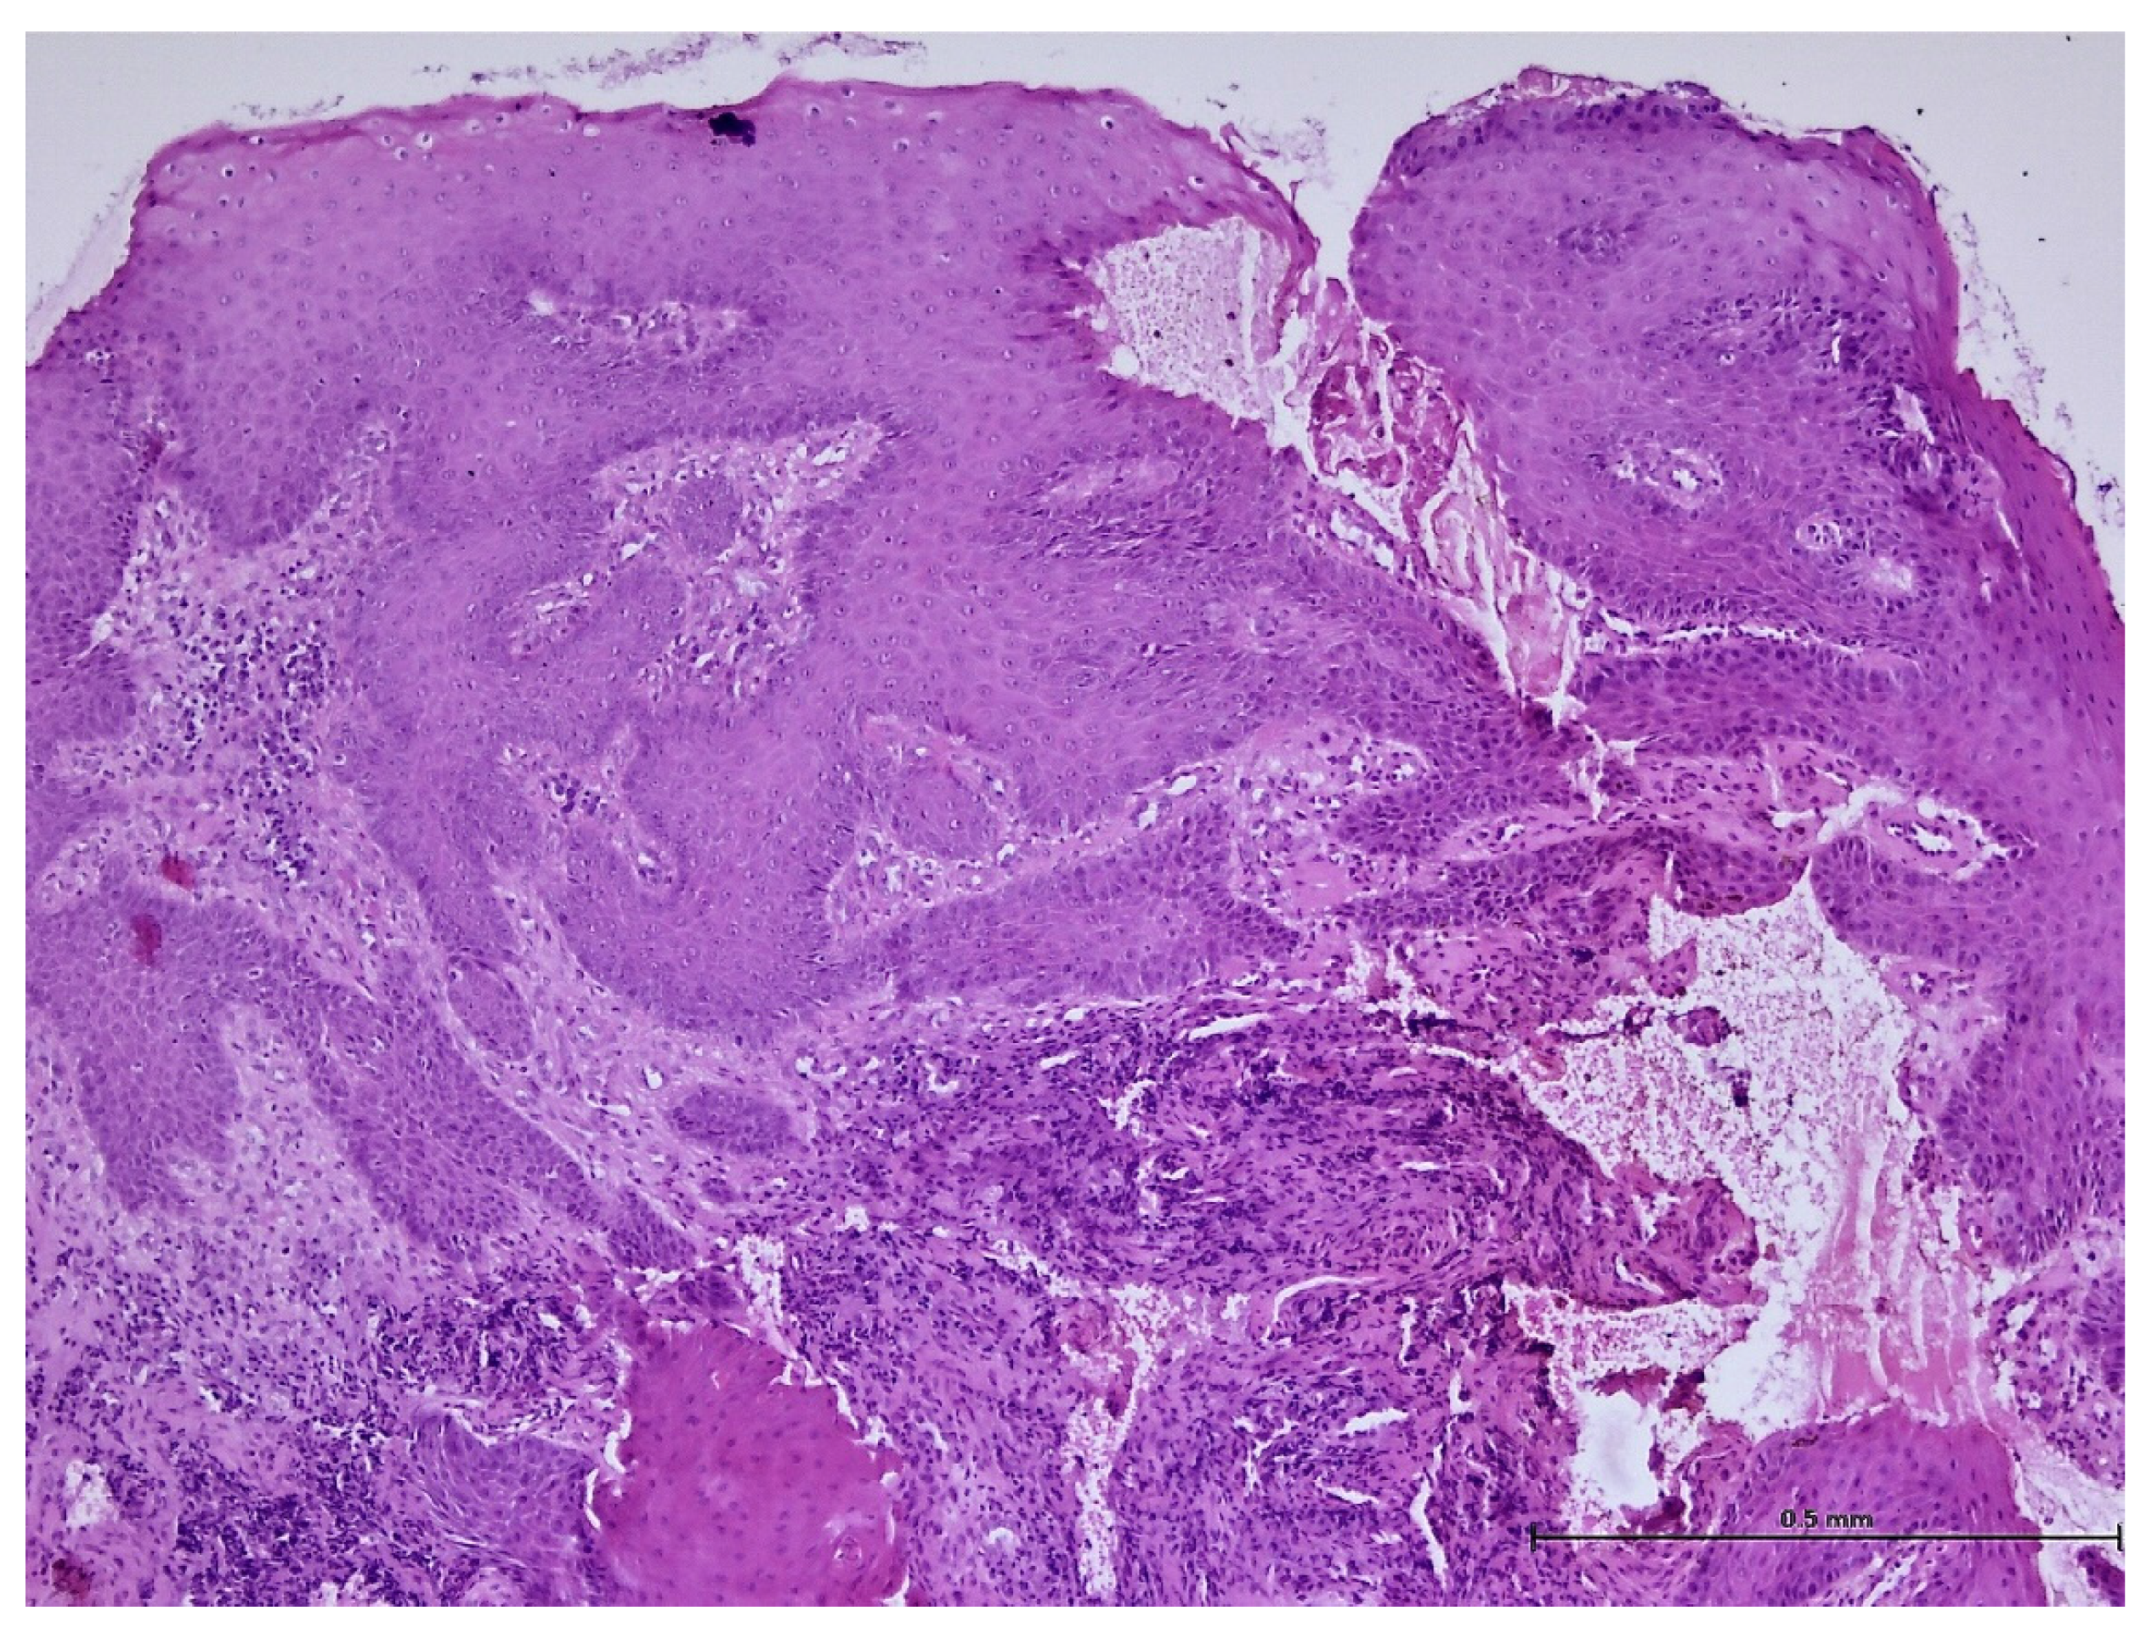

2.4. Histopathological Analysis Protocol

3. Results